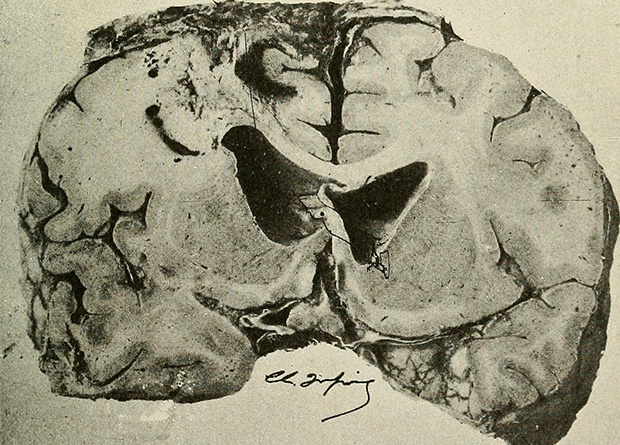

Британские исследователи провели метаанализ 19 исследований с общим участием более 1,5 тысячи человек и выяснили, что оспа обезьян может вызывать судороги, спутанность сознания и энцефалит (воспаление головного мозга, крайне тяжелое состояние, часто приводящее к инвалидности). Результаты работы опубликованы в журнале EClinicalMedicine.